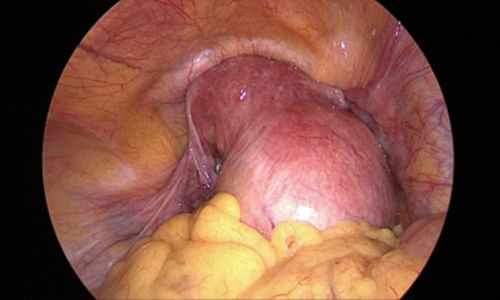

Photo showing a large fibroid in the fundus and body of the uterus:

During surgery, no incisions were made on the abdominal wall. The procedure was performed through the natural birth passage using a hysteroscope, which allowed direct visualisation of the uterine cavity. The fibroid was identified & removed using an energy source.